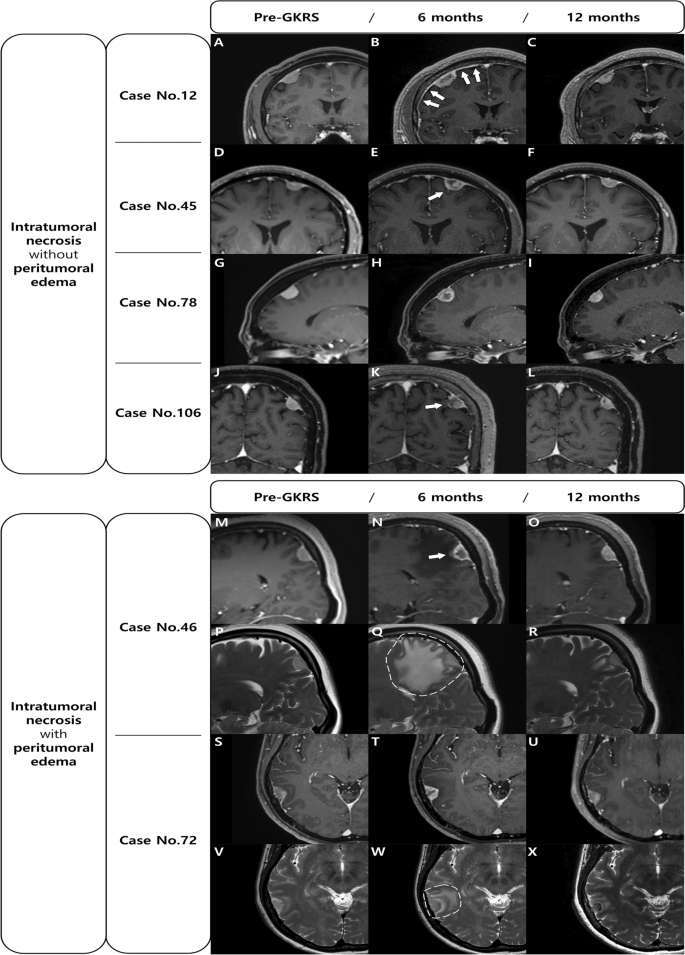

In addition, a dural, arachnoid, or pial enhancement around the tumor was observed in 16 (47.1%) of the 34 patients with meningioma exhibiting ITN (Fig. 1). However, none of the cases of meningioma without ITN showed a meningeal enhancement. There was a significant difference between the two groups (p < 0.001); therefore, we suggest that ITN might be associated with meningeal enhancement. Figure 1 shows the changes before and after GKRS for 4 cases of ITN without PTE and 2 cases of ITN with PTE.

Changes occurring before and after GKRS are shown for 4 cases of ITN without PTE (A–L) and 2 cases of ITN with PTE (M–X). All meningiomas with ITN after GKRS show pseudoprogression with a temporary volume expansion on the follow-up MRI at 6 months (B,E,H,K,N,Q,T,W). ITN may accompany meningeal enhancement (arrows) on T1-weighted images and PTE on T2-weighted images (dotted circles). On the follow-up MRI at 12 months, the ITN has disappeared, the volume is reduced, and the enhancement and PTE are improved. GKRS gamma knife radiosurgery; ITN intratumoral necrosis, PTE peritumoral edema, MRI magnetic resonance imaging.